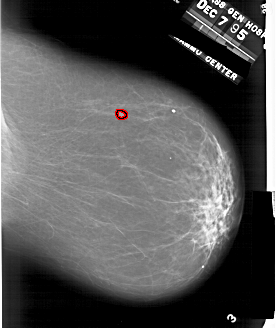

A_1863_1.RIGHT_CC

RIGHT_CC LINES 5896 PIXELS_PER_LINE 4951 BITS_PER_PIXEL 12 RESOLUTION 43.5 OVERLAY

FILE: A_1863_1.RIGHT_CC.OVERLAY

TOTAL_ABNORMALITIES 1

ABNORMALITY 1

LESION_TYPE MASS SHAPE IRREGULAR MARGINS MICROLOBULATED

ASSESSMENT 4

SUBTLETY 4

PATHOLOGY BENIGN

TOTAL_OUTLINES 1

BOUNDARY